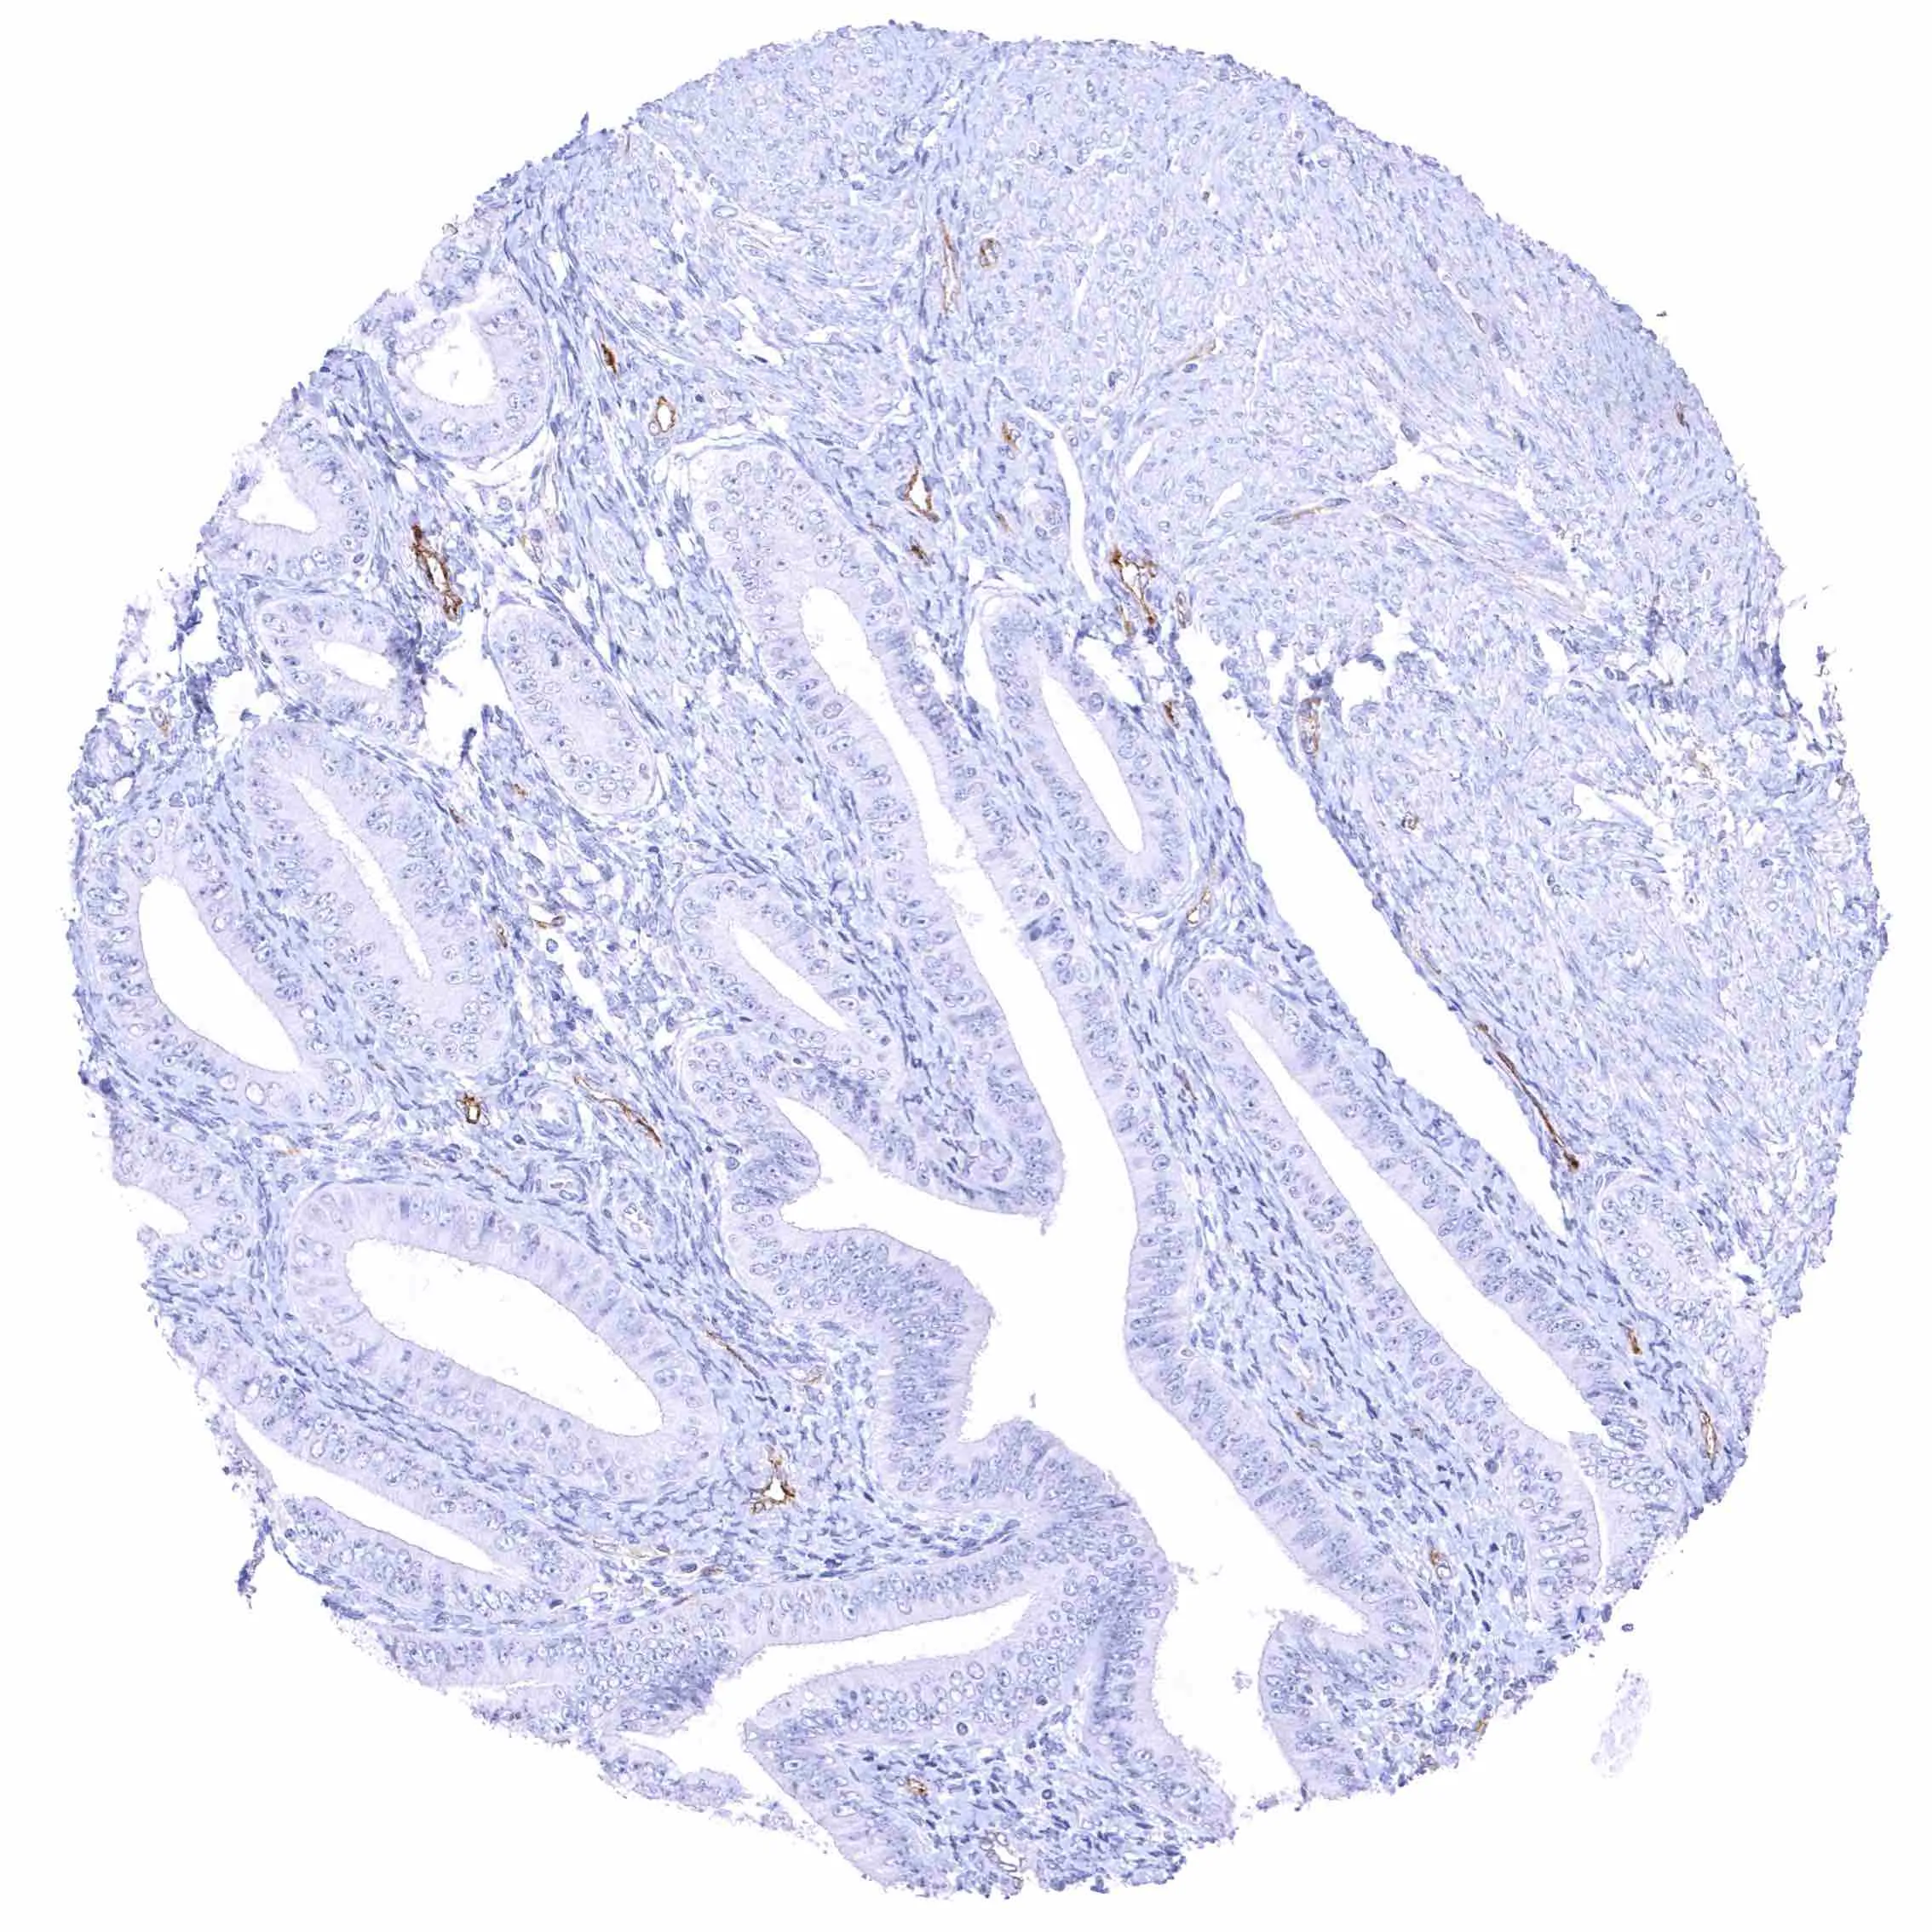

Seminal vesicle – Intense membranous NPR-C staining at the luminal cell border of endothelial cells of small blood vessels.